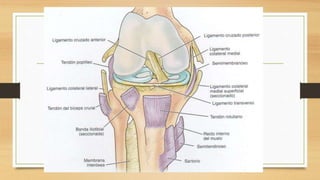

ANATOMIA

CLASIFICACION:

ANTEROMEDIAL:

Capsula medial , LCI, LCA, ligamento oblicuo

posterior

ANTEROLATERAL:

Capsula lateral, LCA, ligamento poplíteo arqueado

POSTEROMEDIAL:

LCI, capsula medial, ligamento poplíteo oblicuo

posterior, LCA, capsula posteromedial

POSTEROLATERAL:

Capsula lateral, LCA, ligamento poplíteo arqueado,

LCL